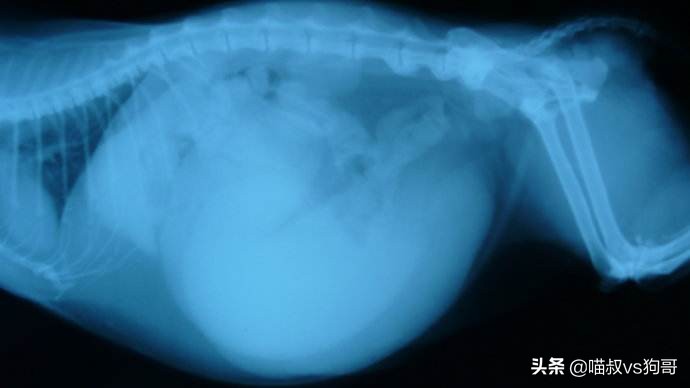

(3) X光片及超声波扫描

仅仅在X光片下不能准确判断是怀孕还是子宫蓄脓的区别,必须借助超声波扫描观察。

X光检查猫咪子宫蓄脓